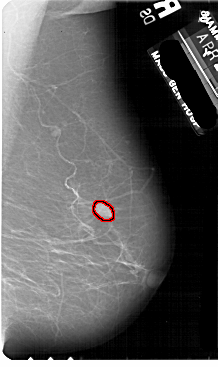

A_1881_1.LEFT_MLO

LEFT_MLO LINES 5491 PIXELS_PER_LINE 3466 BITS_PER_PIXEL 12 RESOLUTION 43.5 NON_OVERLAY

FILE: A_1881_1.RIGHT_MLO.OVERLAY

TOTAL_ABNORMALITIES 1

ABNORMALITY 1

LESION_TYPE MASS SHAPE LOBULATED MARGINS ILL_DEFINED

ASSESSMENT 4

SUBTLETY 4

PATHOLOGY BENIGN

TOTAL_OUTLINES 1

BOUNDARY